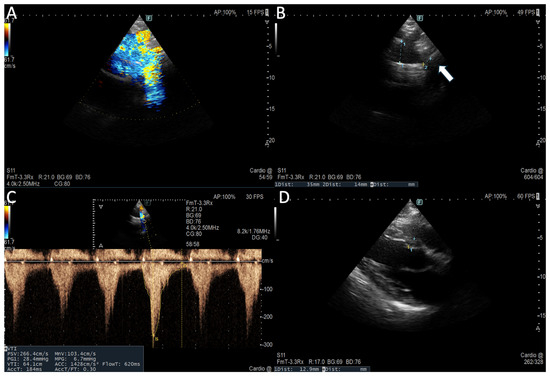

Cardiovascular magnetic resonance (CMR) imaging has emerged as a cornerstone in the non-invasive assessment of cardiac structure, function, and tissue characterization. With its unparalleled spatial resolution, reproducibility, and versatility, CMR enables accurate diagnosis across a wide spectrum of cardiovascular diseases, including cardiomyopathies, ischemic heart disease, myocarditis, valvular disorders (particularly mitral valve prolapse), and congenital anomalies. Beyond diagnosis, CMR is increasingly recognized for its pivotal role in guiding therapeutic decisions—ranging from risk stratification and timing of interventions to monitoring treatment response.

The evolution of advanced techniques such as T1 and T2 mapping, late gadolinium enhancement, strain imaging, and 4D flow has expanded the clinical utility of CMR beyond traditional volumetric and functional assessment. These innovations not only improve diagnostic precision but also enhance our ability to personalize therapy and predict outcomes.